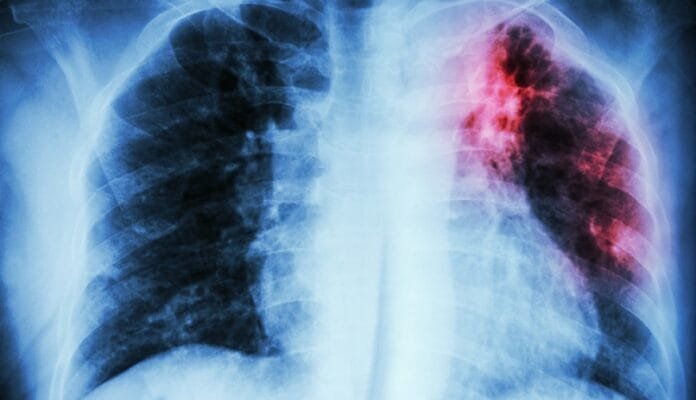

En lo que va de este 2024 existen 41 casos de personas enfermas por tuberculosis en Tierra del Fuego, de los cuales 23 corresponden a la ciudad de Río Grande y 18 a la ciudad de Ushuaia; en tanto que Tolhuin no tiene registros de este tipo de pacientes.

La tuberculosis se ubica en el 6º lugar en el listado de eventos nominales, arrojando una tasa del 21,5 cada 100 mil habitantes.

La Organización Mundial de la Salud (OMS) ha publicado un nuevo informe sobre la tuberculosis que revela que en 2023 aproximadamente 8,2 millones de personas fueron diagnosticadas de tuberculosis por primera vez, la cifra más alta registrada desde que la OMS iniciara el seguimiento mundial de la tuberculosis en 1995.

El informe mundial sobre la tuberculosis 2024 de la OMS pone de relieve los desiguales progresos logrados en la lucha mundial contra la tuberculosis, con desafíos persistentes como una importante infrafinanciación. Si bien el número de muertes relacionadas con la tuberculosis disminuyó de 1,32 millones en 2022 a 1,25 millones en 2023, la cifra total de personas que enfermaron de tuberculosis aumentó ligeramente hasta 10,8 millones, según las estimaciones, en 2023.

Un número considerable de nuevos casos de tuberculosis se debe a 5 factores de riesgo principales: desnutrición, infección por VIH, trastornos por consumo de bebidas alcohólicas, tabaquismo (especialmente entre los hombres) y diabetes. Abordar esos problemas, junto con determinantes críticos como la pobreza y el PIB per cápita, requiere una acción multisectorial coordinada.